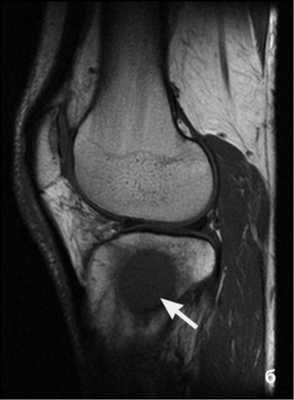

Пациент был направлен на МРТ малого таза с контрастированием (рис. 1). По передней стенке сформированного «предпузыря» определяется дефект размерами 7×8 мм, сообщающийся с расширенным до 10 мм лонным сочленением. Смежные поверхности лонных костей – с признаками отека костного мозга. По нижнему краю расширенного и заполненного жидкостью лонного сочленения определяются два свищевых хода, которые идут на 8 часах условного циферблата (протяженность – до 28 мм) и на 4 часах (протяженность – до 18 мм) книзу и кнаружи с обеих сторон от основания полового члена и слепо заканчиваются в отводящих мышцах. В ветвях седалищных костей – зоны отека костного мозга, в наружных запирательных, приводящих мышцах у лонного сочленения – зоны воспалительной инфильтрации (отмечается накопление контрастного препарата). В пришеечном отделе мочевого пузыря – выраженный отек слизистой оболочки, по левой боковой стенке пузыря на 6 мм кнаружи от устья левого мочеточника – дивертикул 8×9×12 мм. В латеральных массах крестца выявляются симметричные, обширные, продольно ориентированные зоны выраженного отека костного мозга.

С учетом данных МРТ состояние было расценено как остеомиелит лонных костей с источником инфекции в мочевых путях.